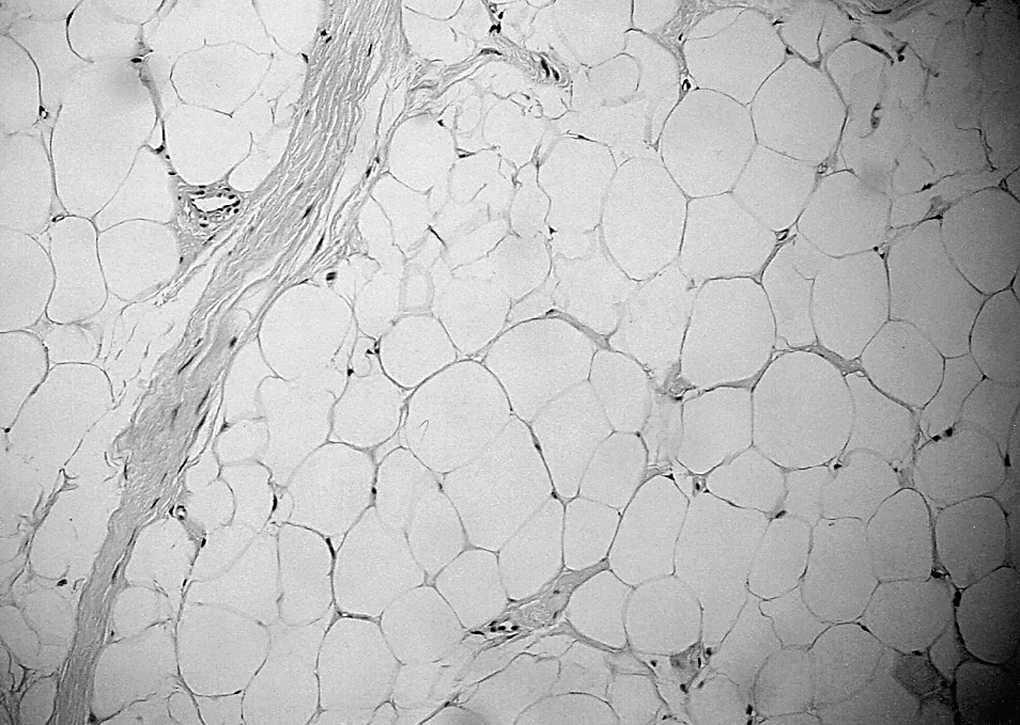

Figura 3. Imagen histológica del lipoma simple. Se observan células grasas maderas sin núcleo atípico y los adipocitos separados por septos fibrosos.